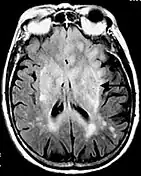

La séquence en inversion-récupération consiste à effectuer une impulsion RF à 180° dans le plan longitudinal avant d'effectuer une séquence écho de spin. Ce type de séquence est notamment utile pour obtenir un meilleur contraste entre les tissus ou bien la suppression du signal de certains tissus comme par exemple le LCR dans la séquence FLAIR (FLuid Attenuated Inversion Recovery)[3] ou de la graisse dans la séquence STIR (Short Time Inversion Recovery)[4].